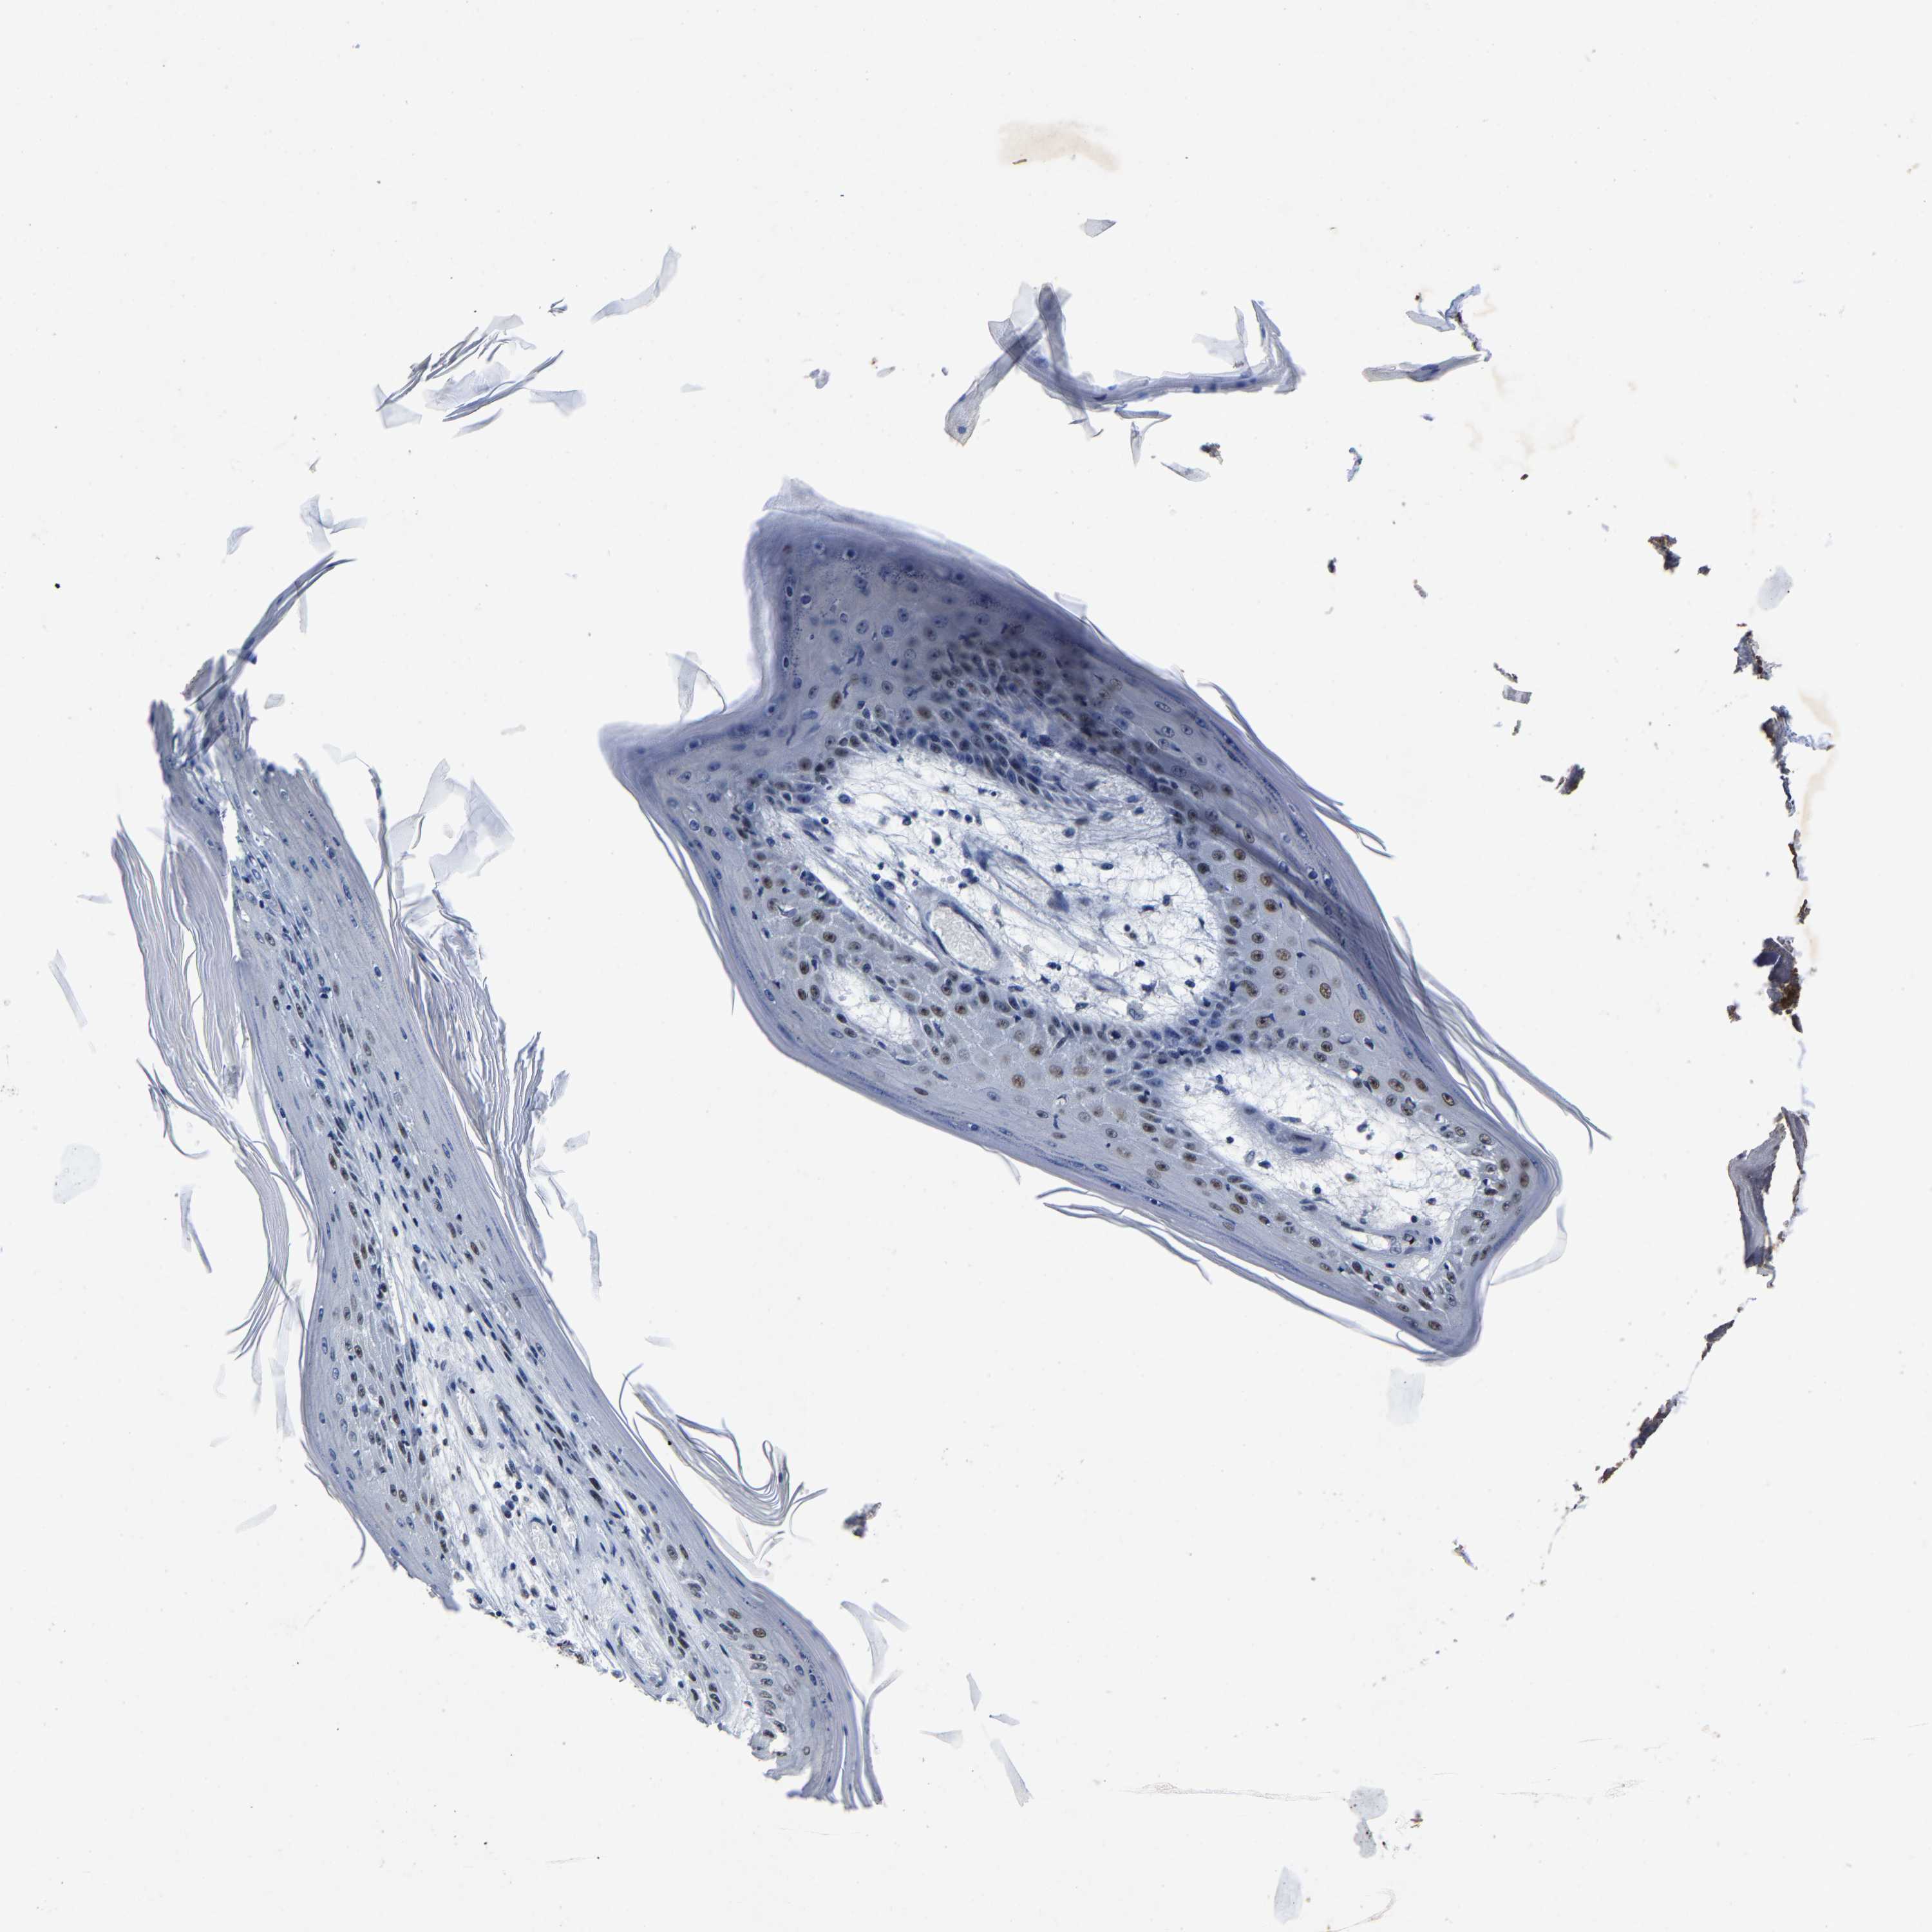

CANCER SKIN CANCER Show tissue menu

Basal cell and squamous cell cancer

SKIN CANCER - Protein expressioni

Antibody HPA020448

Staining

High

Intensity

Strong

Quantity

>75%

Location

Nuclear

Squamous cell carcinoma, metastatic, NOS